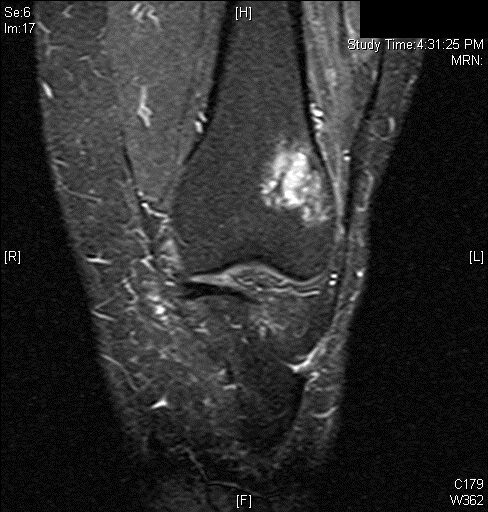

MRI

• MR Imaging, demonstrates intermediate to hypointense signal on T1-weighted images (Fig. 4 & 5) and hyperintensity on T2-weighted images (Fig. 6 & 7).

Fig. 6

Fig. 7

Fig. 6 & 7: MR Imaging. Axial (Fig. 6) and Coronal (Fig. 7) T2 fat saturated image demonstrating T2 hyperintense lesion within the lateral supracondylar femur with a small amount of surrounding bone marrow edema.